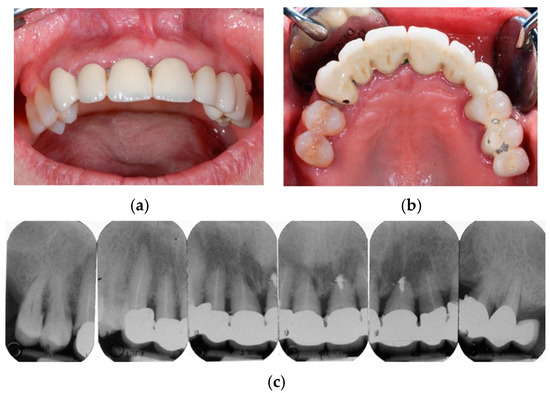

Figure 2. Removal of the fixed bridge before surgical extractions: see roots of the treated elements both from the frontal view (a) and the occlusal view (b).

Figure 3. Surgical extractions with full-thickness mucoperiosteal flap elevation (a), aiming at preserving cortical alveolar walls (especially for the buccal side) with minimal trauma (b).